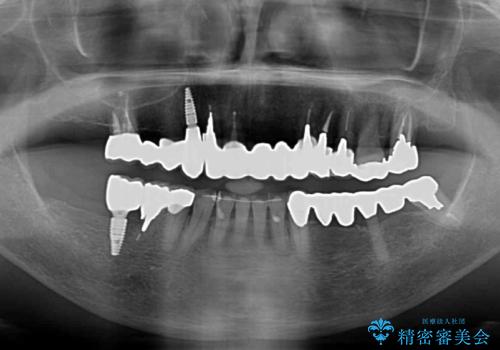

処置を予定していた歯を仮歯に変えた時点で、下顎前歯の部分矯正を行うかどうかを尋ねたところ、折角なので行いたいと言うことでしたので、矯正治療を行うこととしました。

インプラント埋入や根管治療治療など、治癒に一定の期間を要する処置の合間に矯正治療を行うことで、効率的に治療を進めて行くことができました。